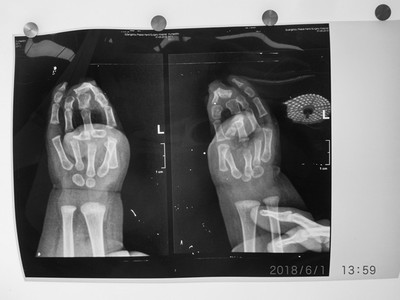

性别:男     年龄:8个月      双手并指畸形

诊断:双手并指畸形,伴活动障碍,需进行并指分指手术